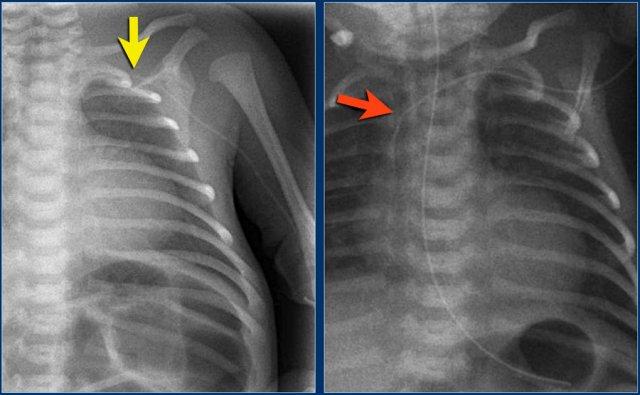

Các phát hiện bao gồm:

- Đường truyền động mạch rốn ở vị trí quá sâu, đầu catheter nằm tại quai động mạch chủ.

- Đường truyền tĩnh mạch rốn với đầu catheter nằm trong nhánh tĩnh mạch cửa phải.

- Đặt sai vị trí đường truyền động mạch rốn vào động mạch chậu trái.

- Đường truyền tĩnh mạch rốn ở vị trí quá sâu, đầu catheter nằm trong nhĩ phải.

- Ống thông dạ dày ở vị trí tốt.